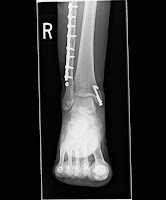

I finally got my x-rays!

I was really excited because I had never seen them before!